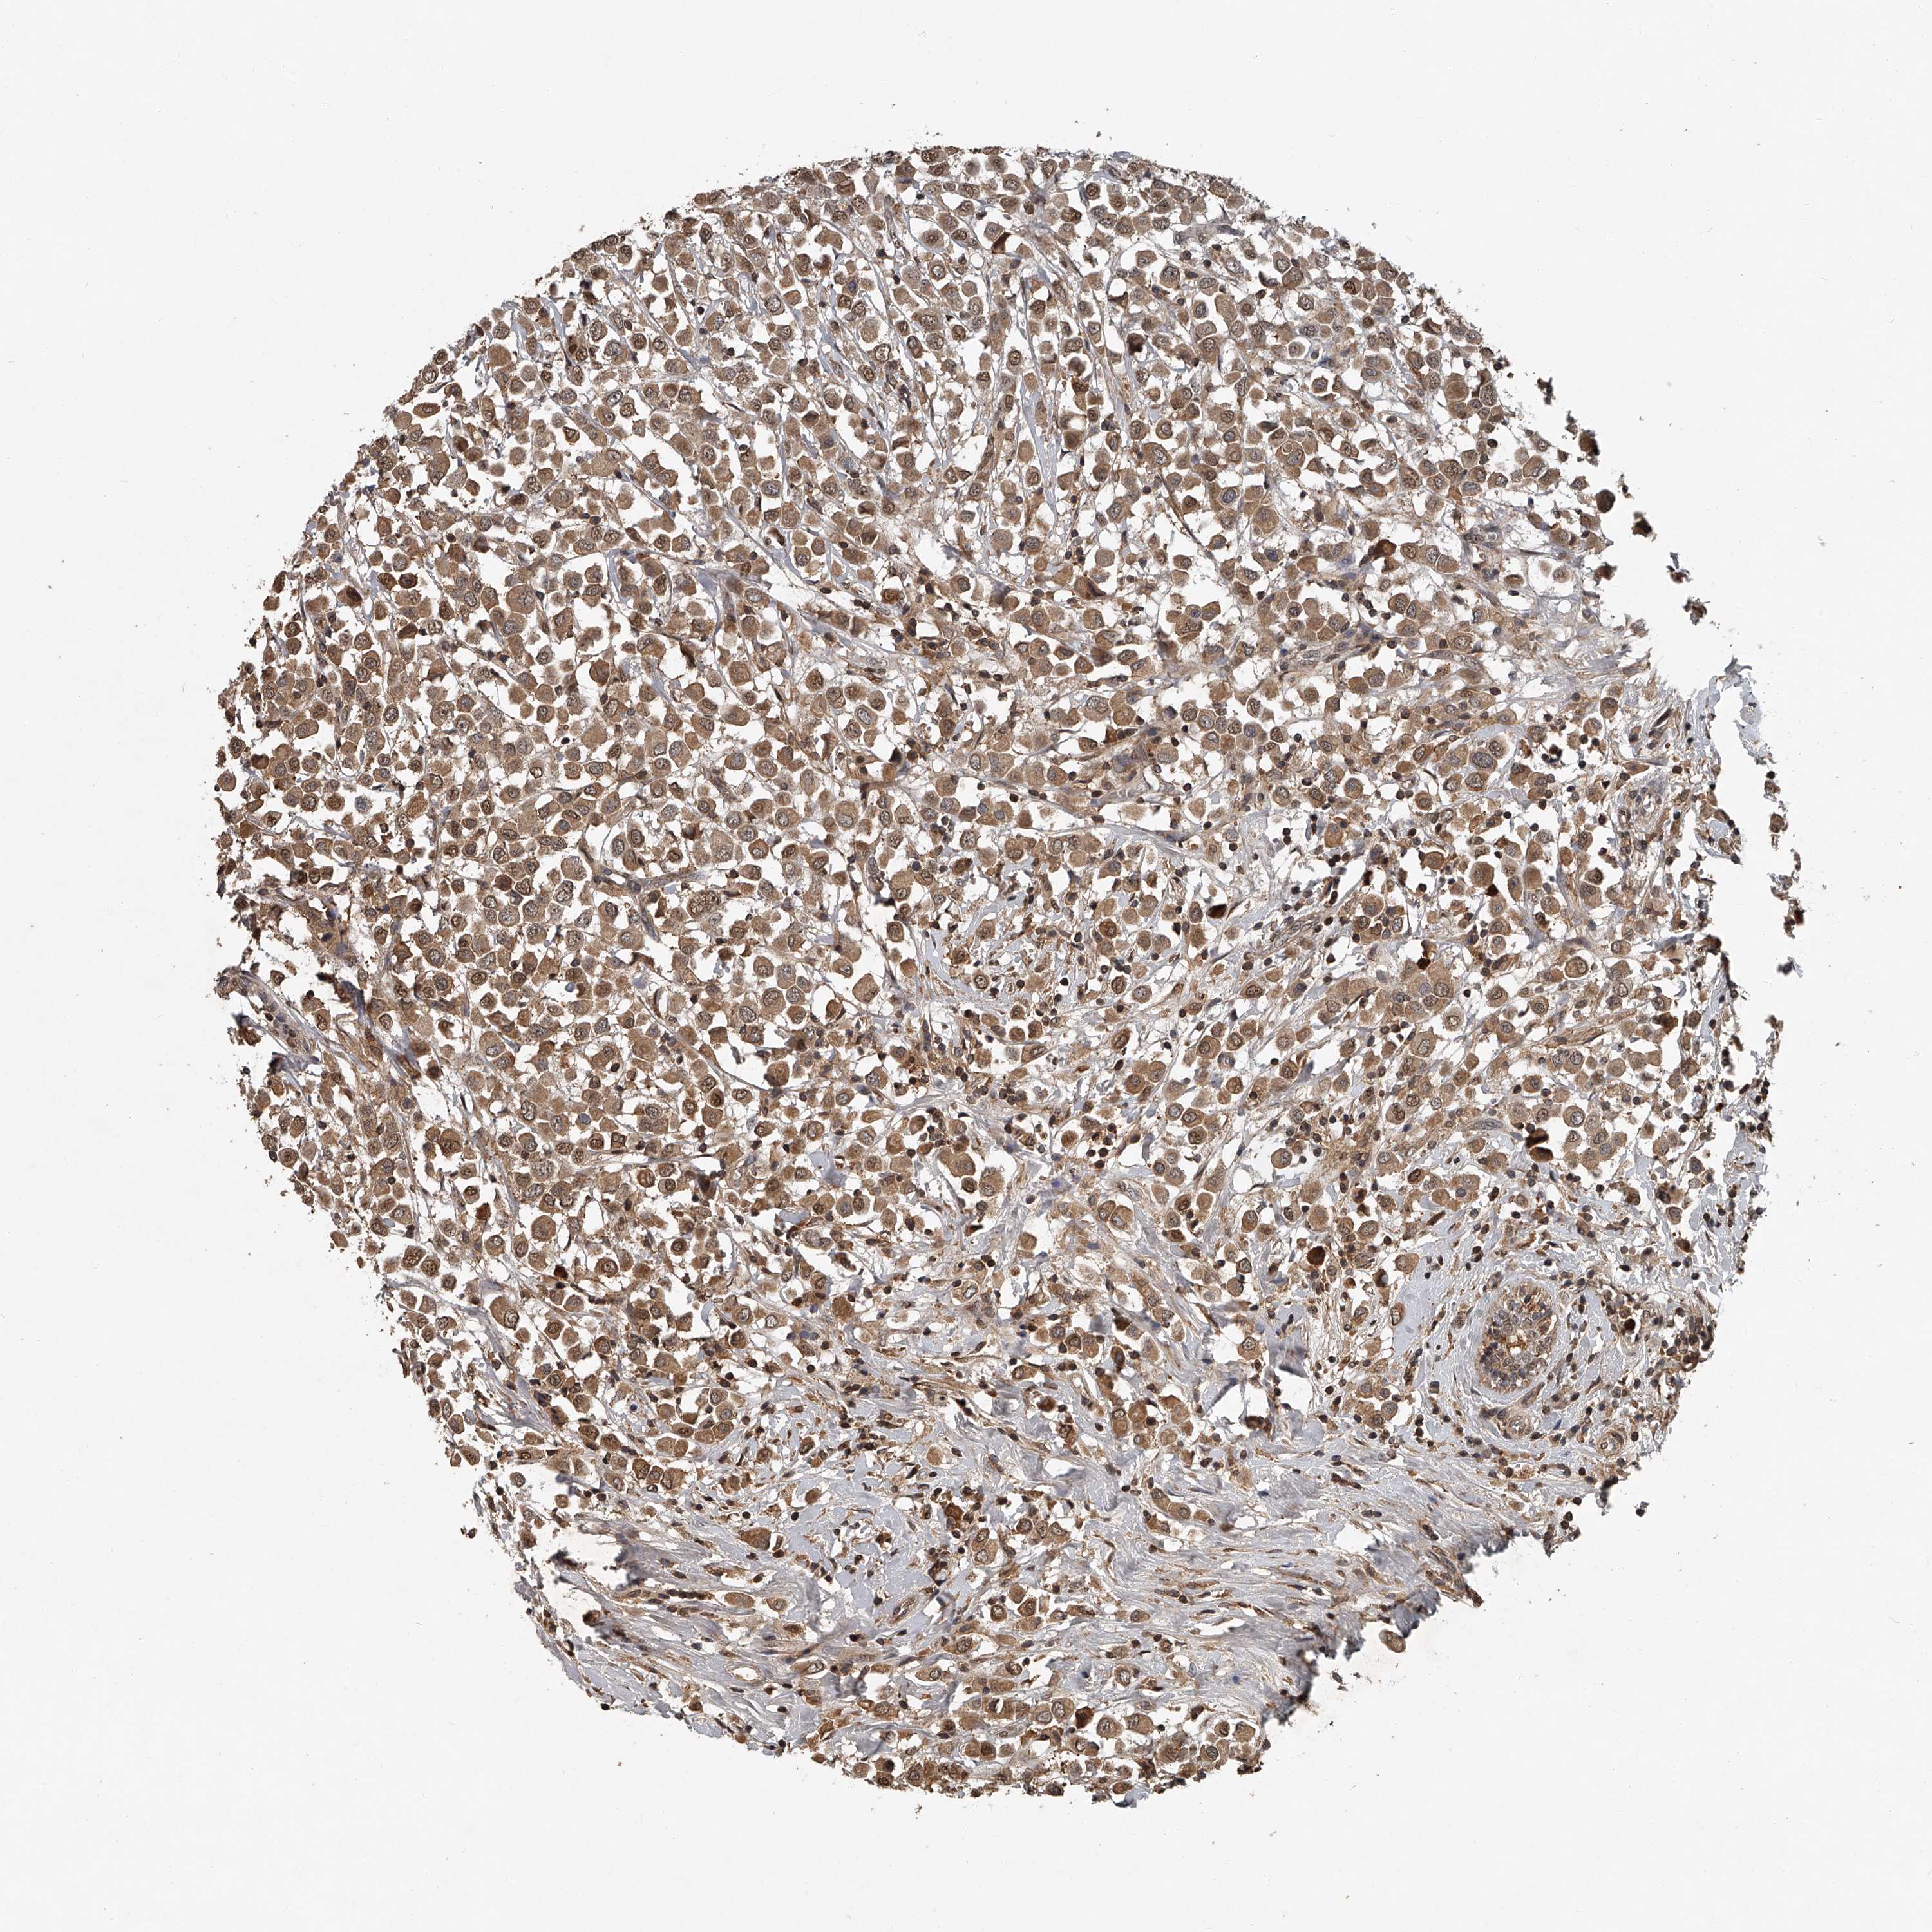

BRCA TCGA BRCA VALIDATION PROTEIN EXPRESSION